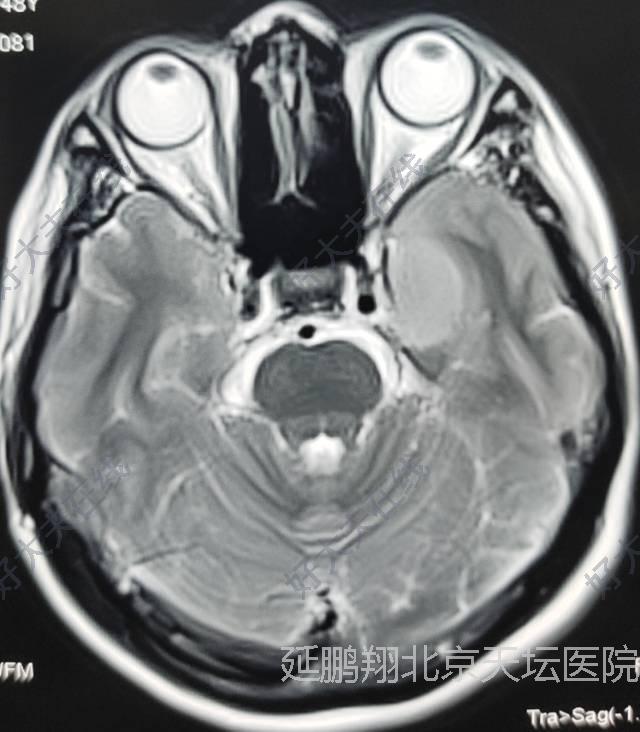

治疗前

女性,48岁。发作性心悸,心烦,头晕11月。CT和MRI显示左侧鞍旁脑膜瘤,与海棉窦及颈内动脉及大脑中动脉关系密切。

左额颞发际边缘弧形切口。术中全切除肿瘤,重要神经血管均保护完好。